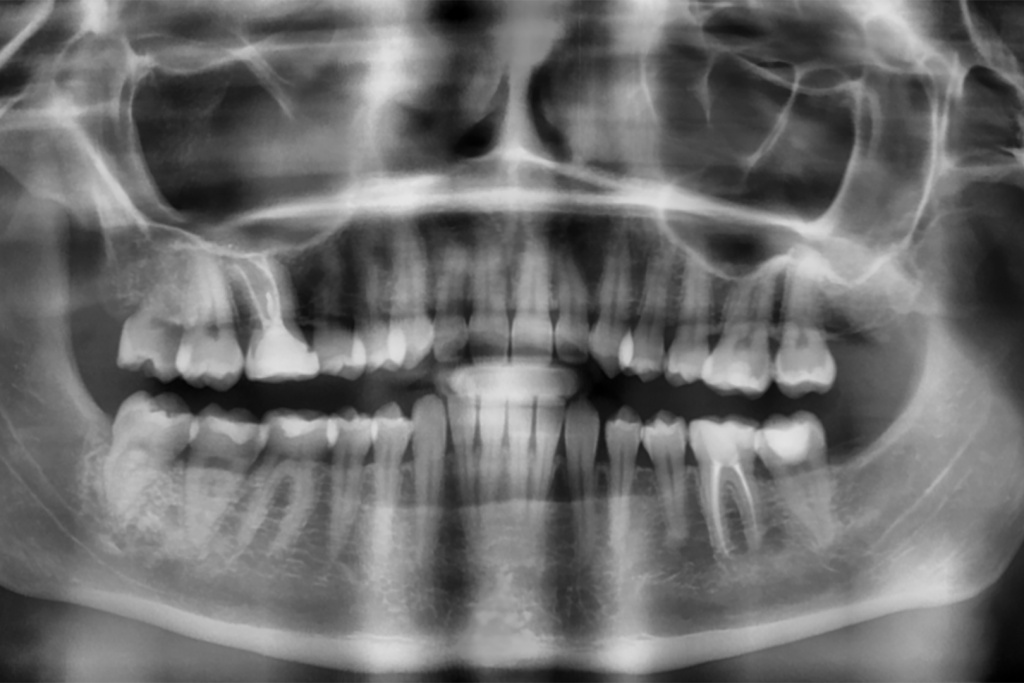

Удаление зуба 3.6

Одномоментная установка дентального имплантата, система Impro